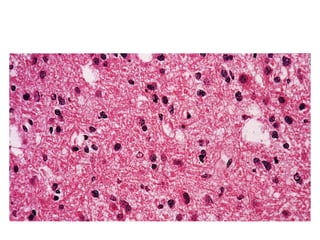

Astrocytoma

1

2

1) Astrocytes with large nuclei and scanty cytoplasm

2) Network of interlacing fibrils